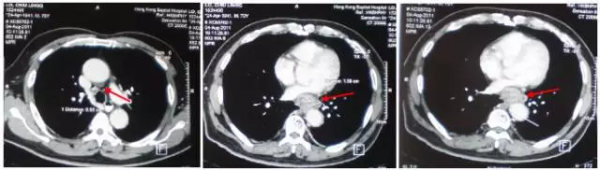

胸腹部CT:食管中段管壁增厚,腫塊與主動脈、心臟關係密切,縱膈及食管旁可見多發淋巴結腫大

CT顯示:食管腫塊明顯縮小,區域淋巴結部分消失